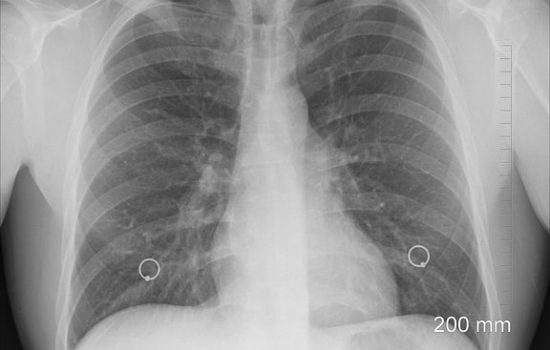

Boala este mai mult decât un set de simptome, este o perturbare a echilibrului natural al corpului tău. Există însă o abordare revoluționară care utilizează frecvențe specifice pentru a combate aceste perturbări direct la sursa lor. Înțelegerea frecvențelor corpului Totul în univers, inclusiv celulele corpului uman, operează la anumite frecvențe. Unele frecvențe pot susține sănătatea